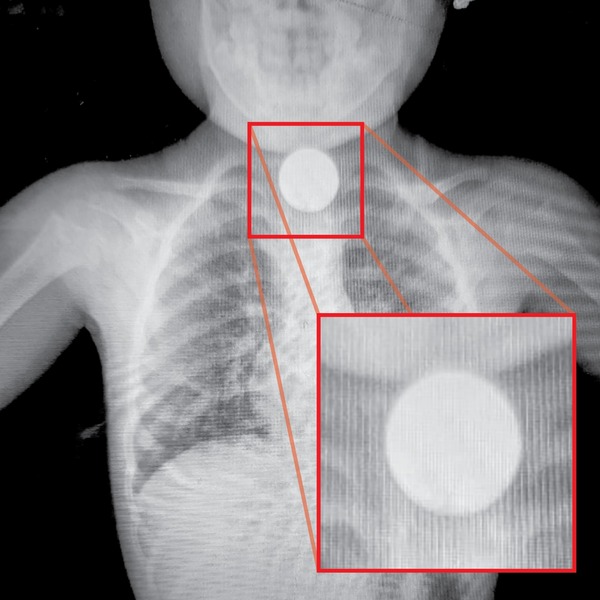

Una niña de dos años, hija de Cinthia Lorena Martínez, vecina del barrio 23 de Octubre, que ingirió una moneda la semana pasada, se encuentra fuera de peligro gracias a la rápida intervención médica... ...[Leer más]